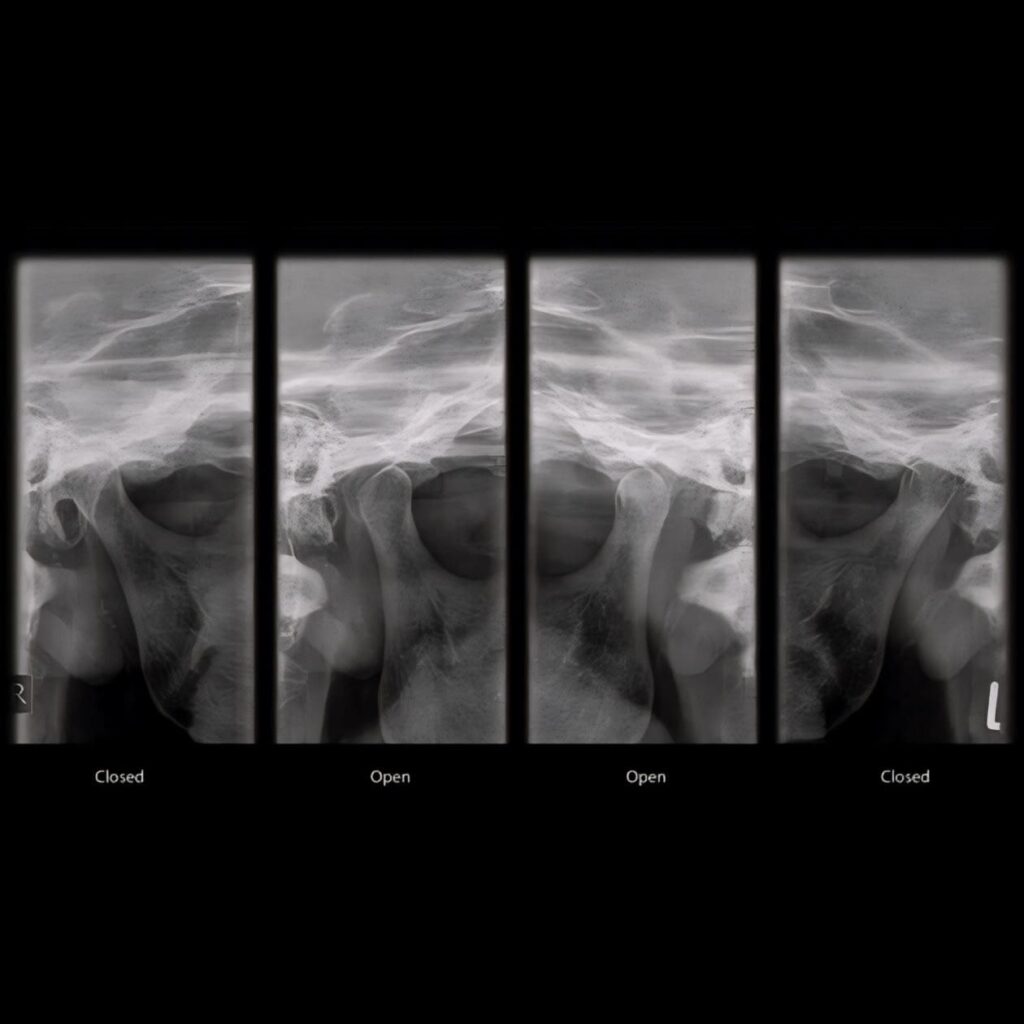

Digital radiographs use electronic sensors to capture images of your teeth, roots, jawbones, and surrounding structures. These images appear instantly on our computers - no film development needed.

We use both intraoral and extraoral digital imaging depending on your needs:

- Intraoral: Bitewing, periapical, occlusal - detailed views inside your mouth

- Extraoral: Panoramic or full-jaw shots as needed